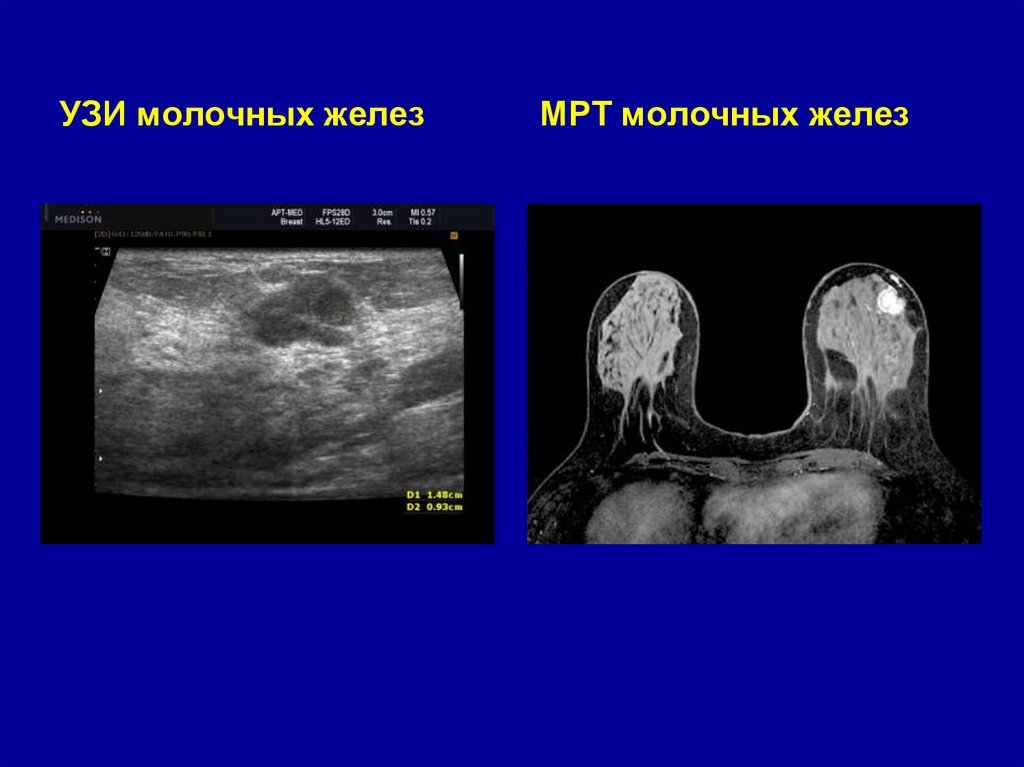

31.

УЗИ молочных желез

МРТ молочных желез